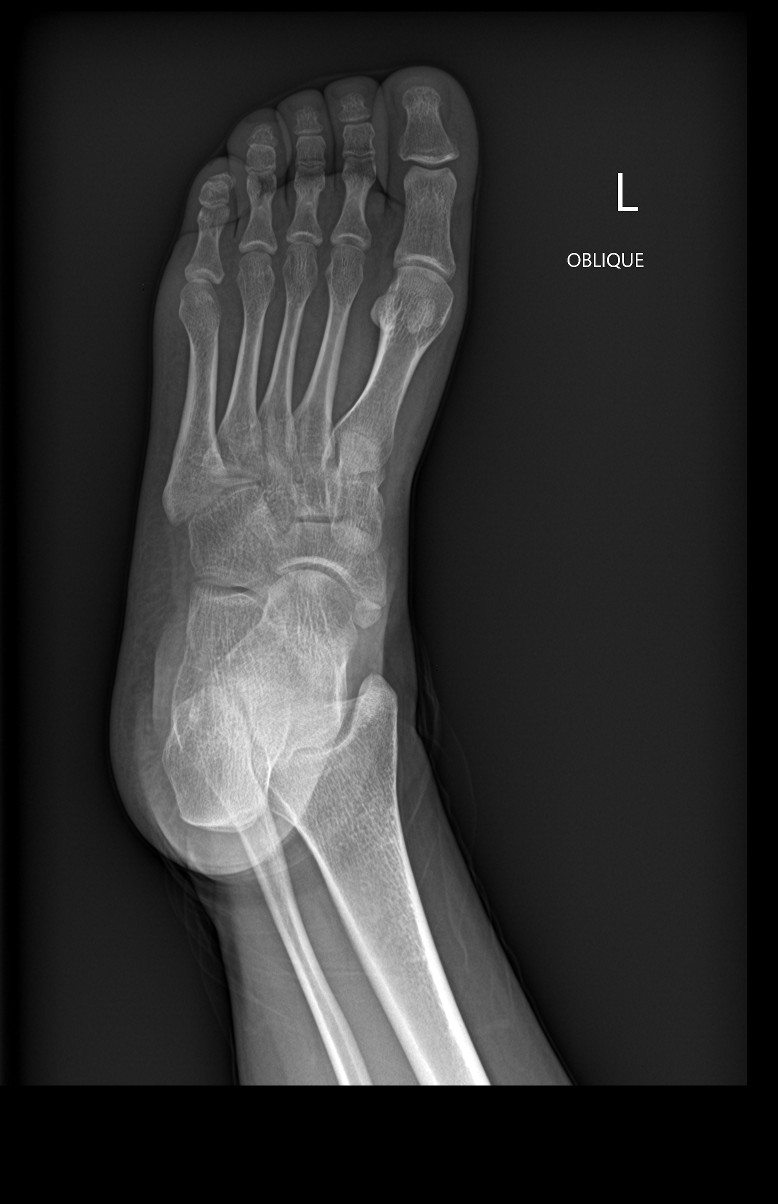

Oblique